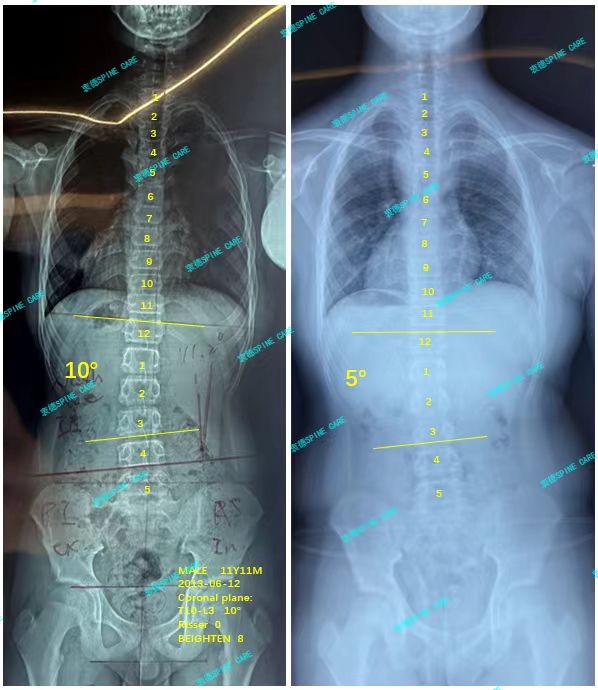

我是轩轩,腰弯从10度降至5度,旋转降低5度,感谢杨博士~

案例主人:轩轩 发现侧弯年龄:12岁 侧弯情况:Cobb角测10°

我坚持训练了3个月,不上课的时候我会每天在家自主打卡,有时候忘记训练康复师姐姐会在打卡群中提醒我训练打卡,我也渐渐地习惯了坚持下来。三个月后的x片让我的坚持也有了成果,我的侧弯从10度下降到5度,旋转也从6度降到了1度,这是非常棒的消息!我们都很高兴~

I persisted in training for 3 months. When I was not in class, I would do simple training myself at home every day. Sometimes, the rehabilitation therapist would remind me to train and check in the check-in group online. I gradually became accustomed to it. The x-ray three months later made my persistence bear fruit. My lateral bending dropped from 10 degrees to 5 degrees, and my rotation also dropped from 6 degrees to 1 degree. This is great news! We are all very happy ~